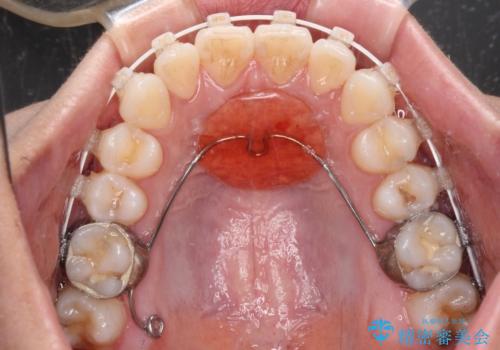

装置はワイヤー装置でもインビザラインのマウスピースでもどちらでも適用でしたが、自己管理の煩わしさを嫌い、ワイヤー矯正にて治療を行うこととしました。

ワイヤー矯正を選択されたため、鋏状咬合を確実に改善するために補助装置を併用することとしました。

ワイヤー装置でもマウスピースでも、どちらでも適用の症例でしたが、片側の鋏状咬合はマウスピース矯正ではしっかりと改善できる可能性が低いことや、何と言っても自己管理の煩わしさがないことから、ワイヤー装置を選択されました。